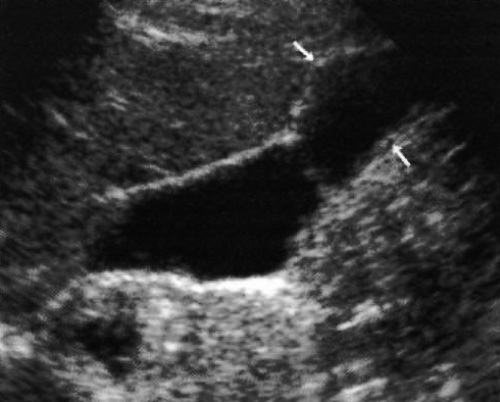

Ультразвуковая картина желчных камней характеризуется гиперэхогенной структурой с задней звуковой тенью (фото 6), что обусловлено способностью желчных камней как поглощать, так и отражать ультразвуковую волну, в результате чего они обладают выраженной эхогенностью и образуют анэхогенную акустическую тень.

Фото 6. Камни в желчном пузыре. На снимке видна выраженная задняя акустическая тень

Отметим, что задняя акустическая тень имеет важное диагностическое значение – эхогенные уплотнения с акустической тенью свидетельствуют о холелитиазе почти в 100% случаев. Желчные камни подвижны (кроме случаев, когда они прилипают к стенке желчного пузыря или застревают в шейке).